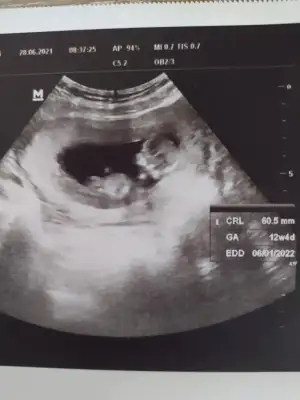

Merhaba Ikra meyra Ikra meyra 12+4 tahminde bulunabilir misiniz 😊 doktor bisey demedi ben de cok arada kaldim sizden de fikir almak isterim💚 ne olursa kabulumuz tabi ki ama merak işte 😁